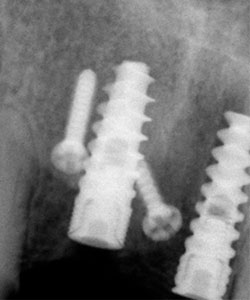

Radiografía Panorámica del paciente, se observa pérdida dentaria y ósea en sector anterior.

Se observa la integración de los implantes, en algunos casos se puede dejar los tornillos de fijación, bien integrados. El paciente está listo para la rehabilitación protésica.